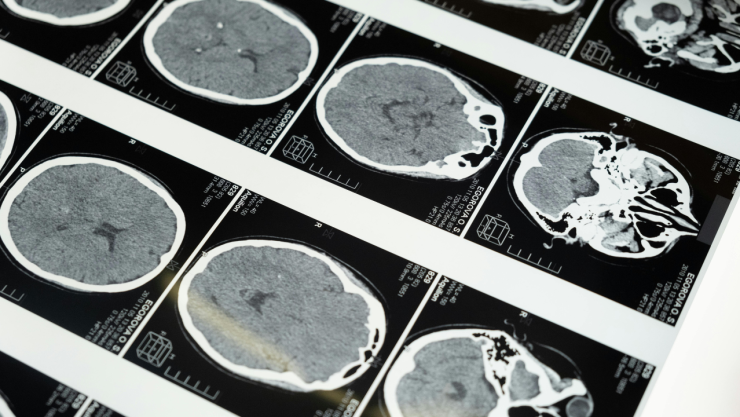

Este 29 de octubre es el Día Mundial del Ictus que es una enfermedad vascular cerebral o también conocida como enfermedad vascular cerebral (EVC).

Es una enfermedad que se presenta cuando el suministro de sangre al cerebro se interrumpe, o disminuye, debido a la ruptura de un vaso sanguíneo, dando lugar a un derrame, impidiendo que el tejido cerebral reciba oxígeno y, en pocos minutos, las células cerebrales mueran.